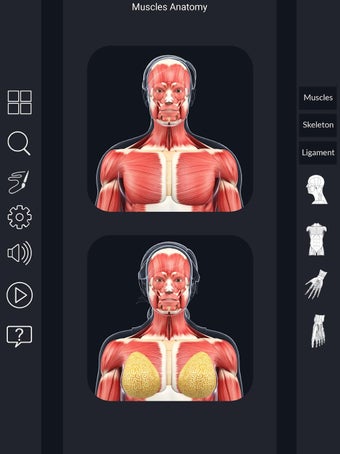

Den mest omfattande mobilappen som finns i världen för att studera muskelanatomi, som låter dig rotera 360°, zooma och flytta kameran runt en mycket realistisk 3D-modell.

Det finns mycket detaljer tillgängliga för varje muskel, vilket gör det till ett utmärkt verktyg för medicinstudenter.

Det finns många verktyg tillgängliga för varje muskel, inklusive:

- Göm och visa varje muskel separat.